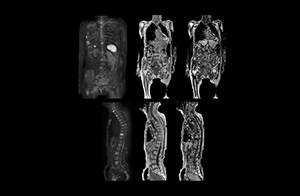

Radiologist Hiroshi Nobusawa, MD, PhD, explains that the coronal DWIBS protocol for whole body DWI is excellent for visualizing lesions in oncology patients. “About 90% of the DWIBS exams are done in this type of patients. The remainder of DWIBS exams are performed to gain information in cases of fevers of unknown origin,” he says. in image acquisition and postprocessing algorithms.”“mDIXON TSE sequences allow simultaneous characterization of morphological changes from the in-phase T2-weighted images and visualization of edematous changes, thanks to the water T2-weighted images from the same acquisition. Anatomical and morphological considerations could be a partial or complete ligament tear, a bony avulsion or hematoma.” “For soft tissue assessment mDIXON brings similar benefits. For example in one T2-weighted mDIXON TSE acquisition, having the multiple contrasts helps us assess abnormalities in peripheral nerves fascicles, which may be due to anatomical or inflammatory changes..” “In peripheral joints, we get good image quality in difficult areas with mDIXON TSE. Fat suppressed images appear homogeneous over the entire image, even with large coverage at 3.0T – for instance in scapular or hip girdles – or in the bearing areas or around metal prostheses*, where fat suppression is often deficient with STIR or spectral fat suppression, causing diagnostic difficulties. If a diagnostic image is right the first time, we don’t need to repeat or add a sequence.” “mDIXON TSE sequences allow simultaneous characterization of morphological changes from the in-phase T2-weighted images and visualization of edematous changes, thanks to the water T2-weighted images from the same acquisition. Anatomical and morphological considerations could be a partial or complete ligament tear, a bony avulsion or hematoma.” “For soft tissue assessment mDIXON brings similar benefits. For example in one T2-weighted mDIXON TSE acquisition, having the multiple contrasts helps us assess abnormalities in peripheral nerves fascicles, which may be due to anatomical or inflammatory changes..”

“The DWIBS sequence’s value in oncology cases is due to the high contrast it creates between lesions and surrounding tissue. Whole body DWI is requested by physicians who need to clarify TNM staging or determine therapeutic strategies, oncologists in need of diagnosis or follow-up scans, surgeons who need to see the presence of distant lesions that are sometimes difficult to detect by CT before surgery, and urologists for the evaluation of bone lesions, and the effect of chemotherapy and radiotherapy.”

“When we limited the scan coverage to the area from neck to femur, we could fit more clinical information in approximately the same scan time. So, we added coronal mDIXON, sagittal T1-weighted, and sagittal STIR sequences to our examination, instead of performing only axial DWIBS and coronal single-shot TSE scans.” The single shot T2-weighted TSE images are used for morphology and compared to DWIBS images to identify T2 shine-through. Sagittal STIR images are used in patients with inflammation or bone metastasis.

“Switching to coronal DWIBS – rather than axial – further shortens scan time,” says Mr. Naka. “Important is that a dS SENSE factor of 5 shortens exam time while high image quality can be maintained, thanks to Ingenia’s dStream architecture.” He adds that the coronal orientation also avoids artifacts that are specific to combining axial images.

“When we use a coronal DWIBS acquisition, we can perform a full whole body examination, including other required sequences, within 30 minutes,” he says.